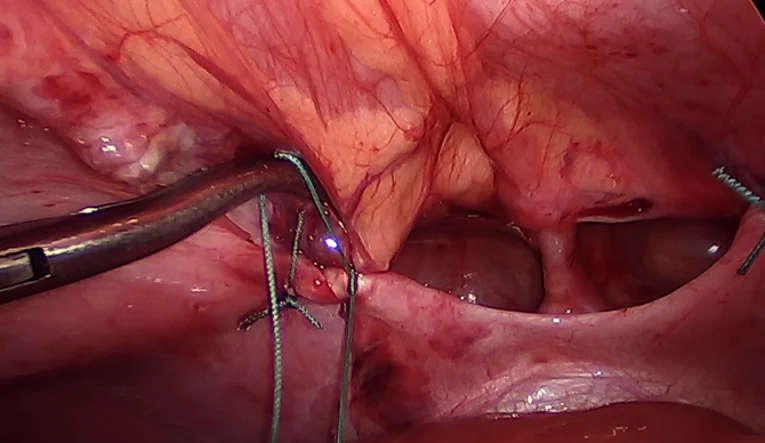

Bei der minimal-invasiven Brustkorbspiegelung werden über 3-4 kleine Schnitte (2-3mm) Arbeitshülsen (Trokare) in den Brustkorb eingebracht. Über diese Arbeitshülsen werden dann eine Kamera und die Operationsinstrumente eingeführt. Damit können unter Kamerasicht die Organe in die Bauchhöhle verlagert und die Lücke im Zwerchfell zugenäht werden.